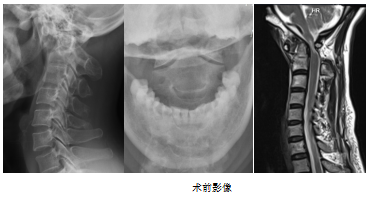

入院后,醫(yī)生為林女士進(jìn)行了詳細(xì)的問診、查體和術(shù)前檢查,擬診“寰樞椎脫位伴不全癱”。

據(jù)了解,寰樞椎位于顱頸交界區(qū),上接顱骨下連頸椎,是連接生命中樞的必經(jīng)之路,一度被視為“手術(shù)的禁區(qū)”。寰樞椎脫位為臨床上比較少見的一種上頸椎疾病,多由外傷、炎癥、腫瘤、退變、先天性畸形等因素引起,嚴(yán)重者導(dǎo)致頸脊髓受壓損傷,進(jìn)而出現(xiàn)高位截等系列由脊髓病變所引起的癱臨床癥狀,更有甚者危及生命。因而,臨床上一旦確診為寰樞椎脫位,在經(jīng)系統(tǒng)保守治療效果不佳的情況下,應(yīng)早期、積極接受手術(shù)治療,以達(dá)到理想復(fù)位、解除脊髓壓迫及維持寰樞椎穩(wěn)定性的目的。

莆田學(xué)院附屬醫(yī)院微創(chuàng)脊柱外科手術(shù)團(tuán)隊經(jīng)過認(rèn)真討論,為林女士制定了周密的手術(shù)計劃,決定為其施行寰樞椎關(guān)節(jié)間融合術(shù)式。此前,首都醫(yī)科大學(xué)附屬宣武醫(yī)院神經(jīng)外科陳贊教授團(tuán)隊開創(chuàng)了寰樞椎脫位治療金標(biāo)準(zhǔn),此項技術(shù)類似頸椎或腰椎的椎間融合技術(shù),更符合Wolff定律。從目前積累治療的兩百多例寰樞椎脫位患者的療效來看,融合率接近百分百。